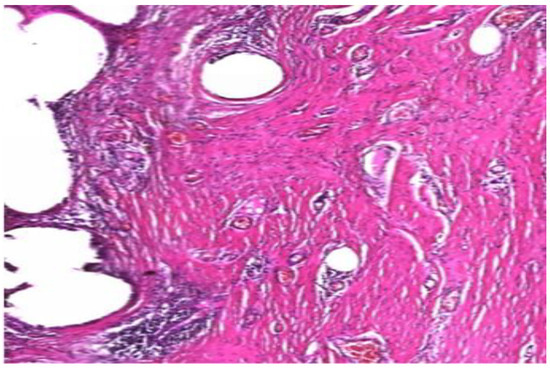

The removed samples were paraffin-embedded, subsequently stained with hematoxylin-eosin and were microscopically analyzed. Fragments of unintegrated mesh revealed adipose connective tissue areas with remnants of synthetic material, with development of small sites of foreign body granuloma in the process of organization through hyaline fibrosis process. The material also presents thin fibrillar structures suggestive for immature type III collagen (Figure 7).

Figure 7.

Synthetic material surrounded by adipose and hyaline tissue, with type III collagen structures. (H and E, ×10).

In cases of poorly integrated meshes images of pronounced inflammatory infiltrate were highlighted, with an increased amount of collagen and fiber width. Properly incorporated areas showed superior connective tissue with a higher amount of type I collagen (Figure 8).

Figure 8.

Important inflammatory infiltrate in the vicinity of the mesh with thicker connective tissue increased amount of type I collagen. (H and E, ×40).